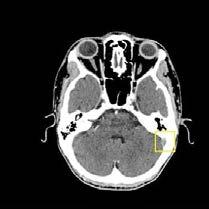

El día 18/2/2022 el paciente refiere dolor torácico. Se realiza un electrocardiograma, que muestra elevación del segmento ST en las derivaciones anteriores en relación con un infarto agudo de miocardio (IAM) anterior. Se activa código infarto y se realiza una coronariografía emergente, que muestra una oclusión de perfil embólico en la arteria descendente anterior media (Figura 1, flecha amarilla). Se trata con trombectomía aspirativa con buen resultado angiográfico final con flujo TIMI 3. Se inicia tratamiento con perfusión de heparina sódica. El día 19/2 el paciente comienza con cefalea muy intensa y afasia, por lo que se activa nuevamente código ictus y se realiza un angioTAC craneal que muestra una hemorragia subaracnoidea (HSA) de predominio izquierdo secundaria a sangrado por un aneurisma disecante de la rama M2 de la arteria cerebral media izquierda (Figura 2, flecha amarilla). Se decide completar estudio con una angiografía que confirma los hallazgos del TAC. Por el alto riesgo de resangrado y la necesidad de anticoagulación oral permanente, se decide embolización del aneurisma con coils, que resulta exitoso (Figura 3, flecha amarilla). Se reinicia durante el ingreso perfusión de heparina sódica y unos días antes del alta se comienza con anticoagulación oral con apixaban 5 mg/12 horas. La evolución clínica es favorable, siendo la exploración física al alta normal. Tras tres años de seguimiento bajo tratamiento con apixaban 5 mg/12 horas no han sido reportados nuevos episodios de sangrado ni de trombosis.

Se realizó una tomografía computarizada (TC) con contraste de forma emergente, que mostró una disección aórtica iatrogénica tipo A focal de origen en la zona 0 del cayado con extensión al tronco braquiocefálico derecho (1) sin afectar al resto de troncos supra-aórticos, cayado o aorta descendente (Figuras 1 y 2); además del hematoma

Figuras 1 y 2: Prótesis aórtica migrada y disección aórtica focal tipo A, de origen en la curvatura menor del arco aórtico (zona 0) hasta la bifurcación de la arteria braquiocefálica derecha; sin afectación de del resto de troncos supra-aórticos, del resto del cayado aórtico o de la aorta descendente.